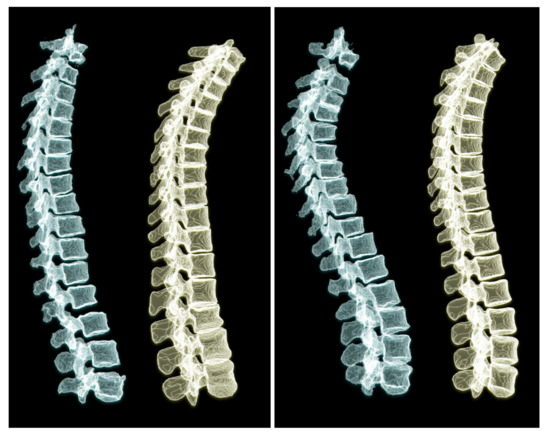

To appreciate the difference of spine posture in the standing and lying down positions, we illustrate the two cases we used in this experiment in Figure 12. The spine postures reconstructed from radiographs in upright standing position are depicted on the left and the ones from CT are depicted on the right side of the figure.

First, as explained in the results section (Figure 9) the model performance drops for lumbar vertebrae in all models because of few lumbar vertebrae in the lung-centered dataset we used. Second, the sagittal and coronal view radiographs might not be perfectly perpendicular in clinical settings; whereas, we generated DRRs with orthogonal projection angles.

Training the model with a dataset containing more scans with lumbar vertebrae, could improve the model performance in the lumbar region. As depicted in Figure 12, we compared the standing and lying down spine postures of two patients. Acquiring more annotated pairs of CT scans and radiographs of the same patient could enrich the results and provide more data for validation. We use a relatively large-scale dataset for training our model. Although the size and anatomical variations in patients helps the model learn the shapes and deformations, we believe that data augmentation by adding a small randomness to the projection angle in the simulated radiographs could teach the model this randomness in clinical radiographs.

Figure 12. Comparing 3D reconstructions of the standing spinal posture from clinical radiographs (left, green) to the spinal posture of the same patient in lying-down position from CT imaging (right, yellow) in two different patients. In the upright-standing posture the spine is under natural weight bearing, which leads to a different spine curvature.